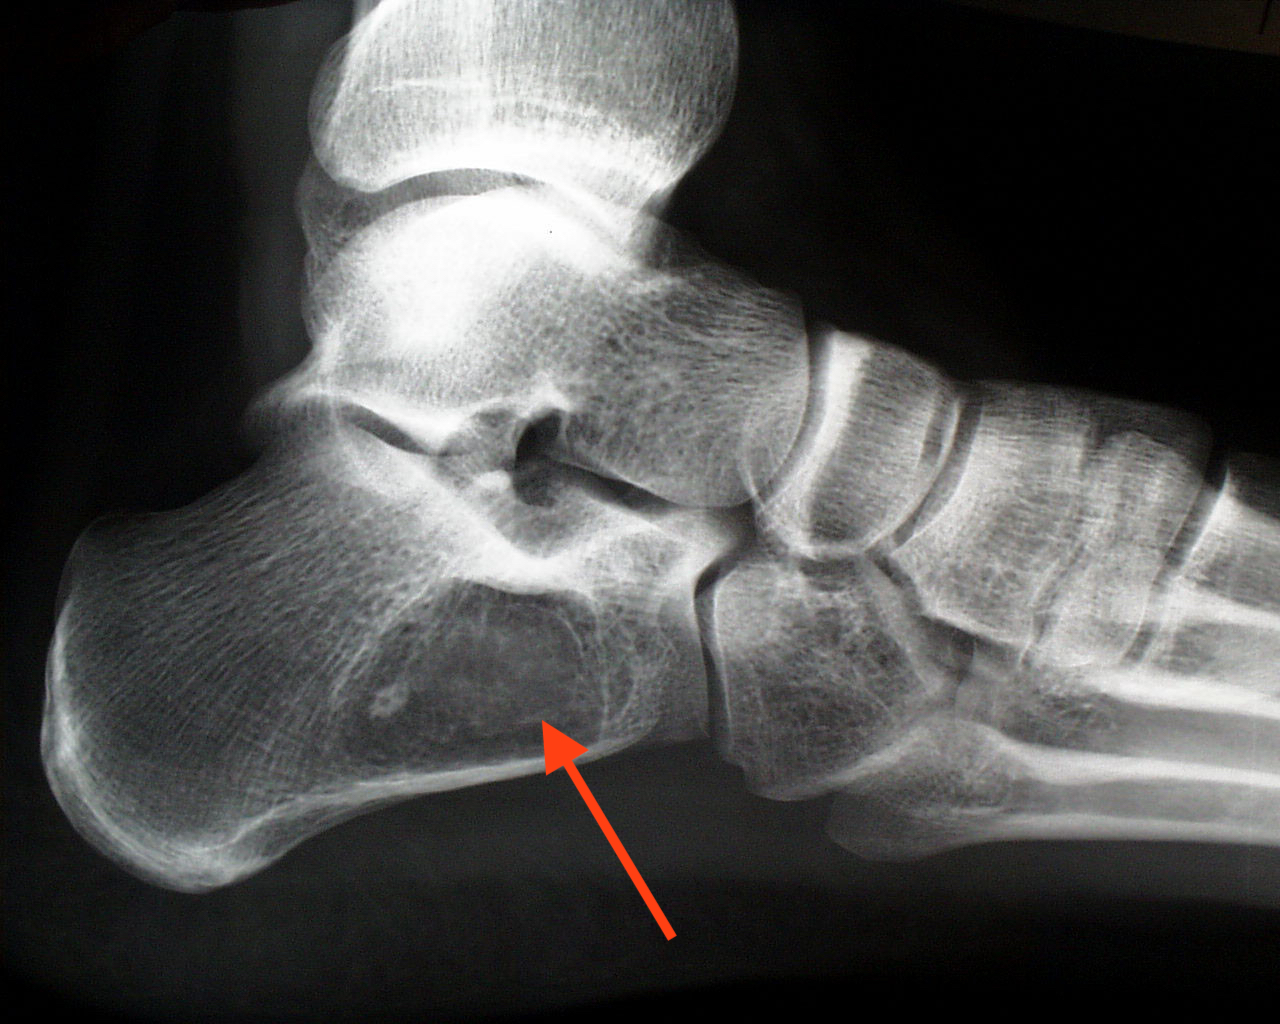

There are multiple forms of malignant cancer that can afflict tissues in the foot, as well as multiple forms of benign cancer. The more common of these uncommon diseases include malignant cancer of or in bone (osteosarcoma, Ewing’s sarcoma), and of muscle (rhabdomyosarcoma). Benign tumors in this list include masses in bone (osteochondroma, enchondroma, bone cysts), and in fibrous tissue, fat tissue, and blood vessels.

The more serious bone cancers tend to be seen in teenagers, while benign masses tend to be seen in younger children. The symptoms often include pain, local warmth in the skin, and sometimes swelling or the appearance of a lump over the tumor site. Diagnosis begins with a simple exam and x-rays, and further testing is performed if a tumor is suspected. Malignant tumors can threaten the leg, and can potentially spread to other organs, including the lungs, leading to death. Early treatment is vital to saving the affected leg and the child’s life. Benign tumors usually cause little in the way of real problems, but may be painful depending on their size and location and sometimes they have to be removed.